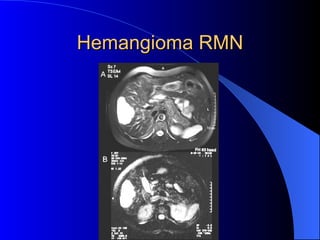

Hemangiomas  Tumor benigno mas frecuente. Mayor incidencia en mujeres Asintomaticos. Cirugia solo sin el paciente esta  sintmatico o presenta sindrome de  Kasabach – Merritt (Trombocitopenia mas hipofibrinogenemia)

Hemangioma RMN

Hemangioma

Hemangioma Hepático